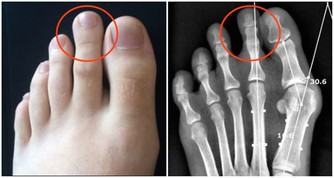

5. 更容易罹患致命疾病

如果你長期晚睡,身體會分泌更多的皮質醇激素,這種激素在壓力狀態下可以保命。比如看到老虎我們拔腿就跑,而且跑得飛快,這是皮質醇的功勞。但皮質醇水平長期偏高,意味著你的血壓、血糖可能升高,更容易出現高血壓、糖尿病甚至癌症等,對心臟健康也非常不利。所以,那些早睡的人,出現動脈硬化的風險要比晚睡者小,而且更不容易被猝死找上。